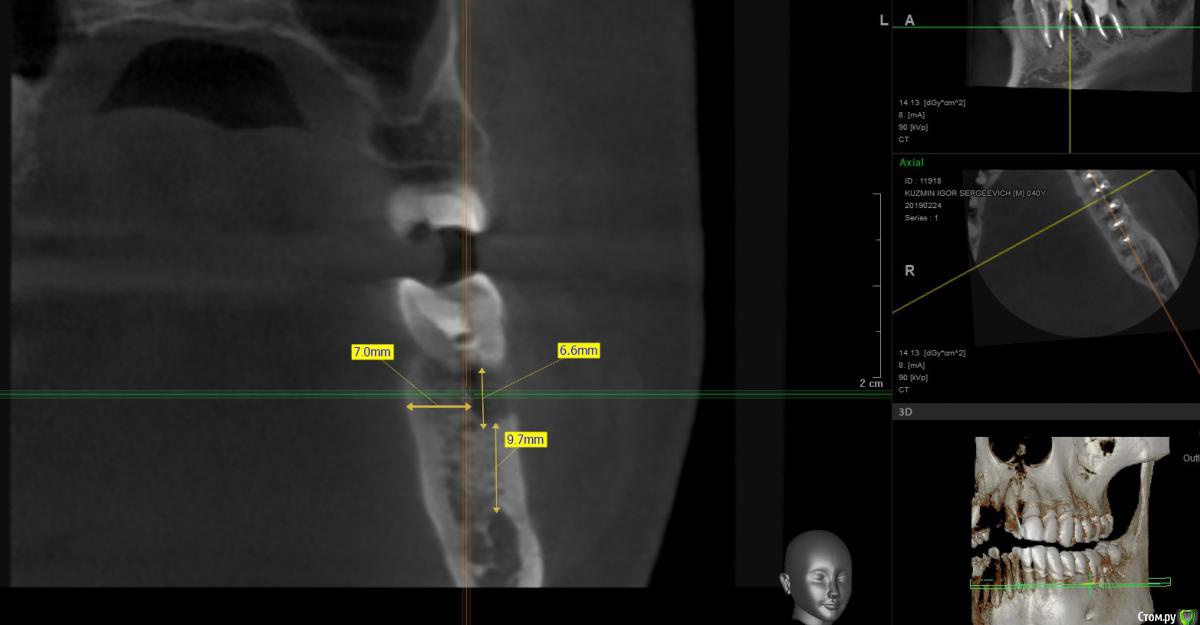

isk0 Опубликовано 10 марта, 2019 Поделиться Опубликовано 10 марта, 2019 Так случилось, что с пол года назад на десне 6 зуба образовался свищ. Обратился к врачам порекомендовал кто-то удалить 6 зуб. По глупости своей решил попробовать сделать лоскутную операцию на этот зуб. Все почистили, помыли, но зуб снова воспалился через две недели.В это время я перелечивал каналы соседнего 7-го зуба и 5-го зуба. По прошествии 5 месяцев закончив лечить другие зубы, я сделал контрольное кт и когда я сравнил оба кт с разницей 5 мес. я увидел следующее Мало того, что под 6 зубом убыль кости спрогрессировала, так еще не понятно, что произошло с 7 зубом...В общем я снова по врачам,Один врач сказал удалить 6 и 7 зуб и через два месяца ставить туда имплантаты. Ок подумал я, но меня смутило, врач меня заверил костной пластики на 6 зуб не нужно будет поставит так..., по 7 зубу вопросов нет.Второй врач сказал удалить 6 зуб, заложить костный материал на его место и накрыть мембраной, заодно почистив область бифуркации 7 зуба. И ждать 3-4 месяца результата. В том числе он меня уверил что убыль кости в фуркации 7-го зуба связана с 6-м зубом (это и так понятно). И если убрать 6 зуб, разрежение фуркации 7-ки остановится и что воспалительного процесса там нет и тем более кисты.срез кт по 7-му зубу И вот уважаемые доктора я на перепутье. Однозначно только одно понимаю, что 6-ку удалять. Но как быть с 7 зубом и нужна ли все таки костная пластика на 6-ку послу удаления.... Короткий имплант не поставишь все таки зуб большую нагрузку несет жевательную, под углом мастерить тоже что-то не хочется, а ставить полноценной длины 10 мм и более , слишком близко канал нижнечелюстного нерва идет , не хочется вечную анестезию получить. Заранее спасибо. Ссылка на комментарий

Борис80 Опубликовано 12 марта, 2019 Поделиться Опубликовано 12 марта, 2019 Неудобные срезы, короткий имплант это 6 мм , у вас там больше, имплант 8-8.5 мм и более это уже отличной длины, достаточной для жевательного зубав области верхушек 7 есть воспаление, но данных недостаточно, чтобы сказать однозначно Ссылка на комментарий